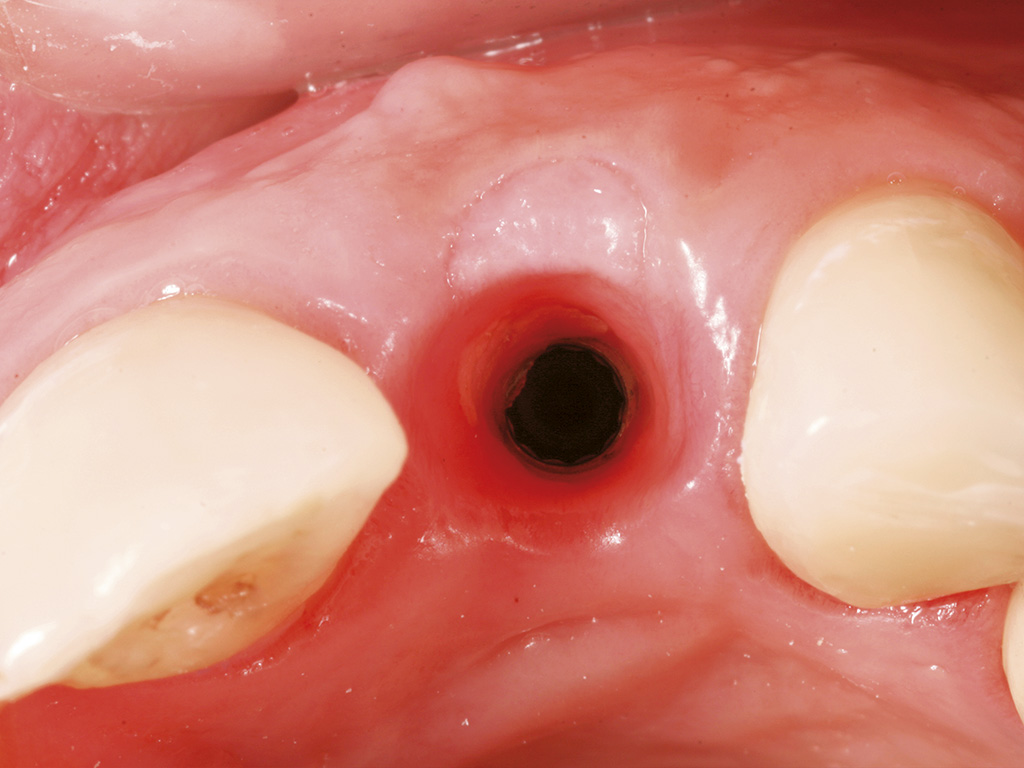

Figure 1 Appropriate asceptic handling of bone substitute materials

- Figure 1 Appropriate asceptic handling of bone substitute materials